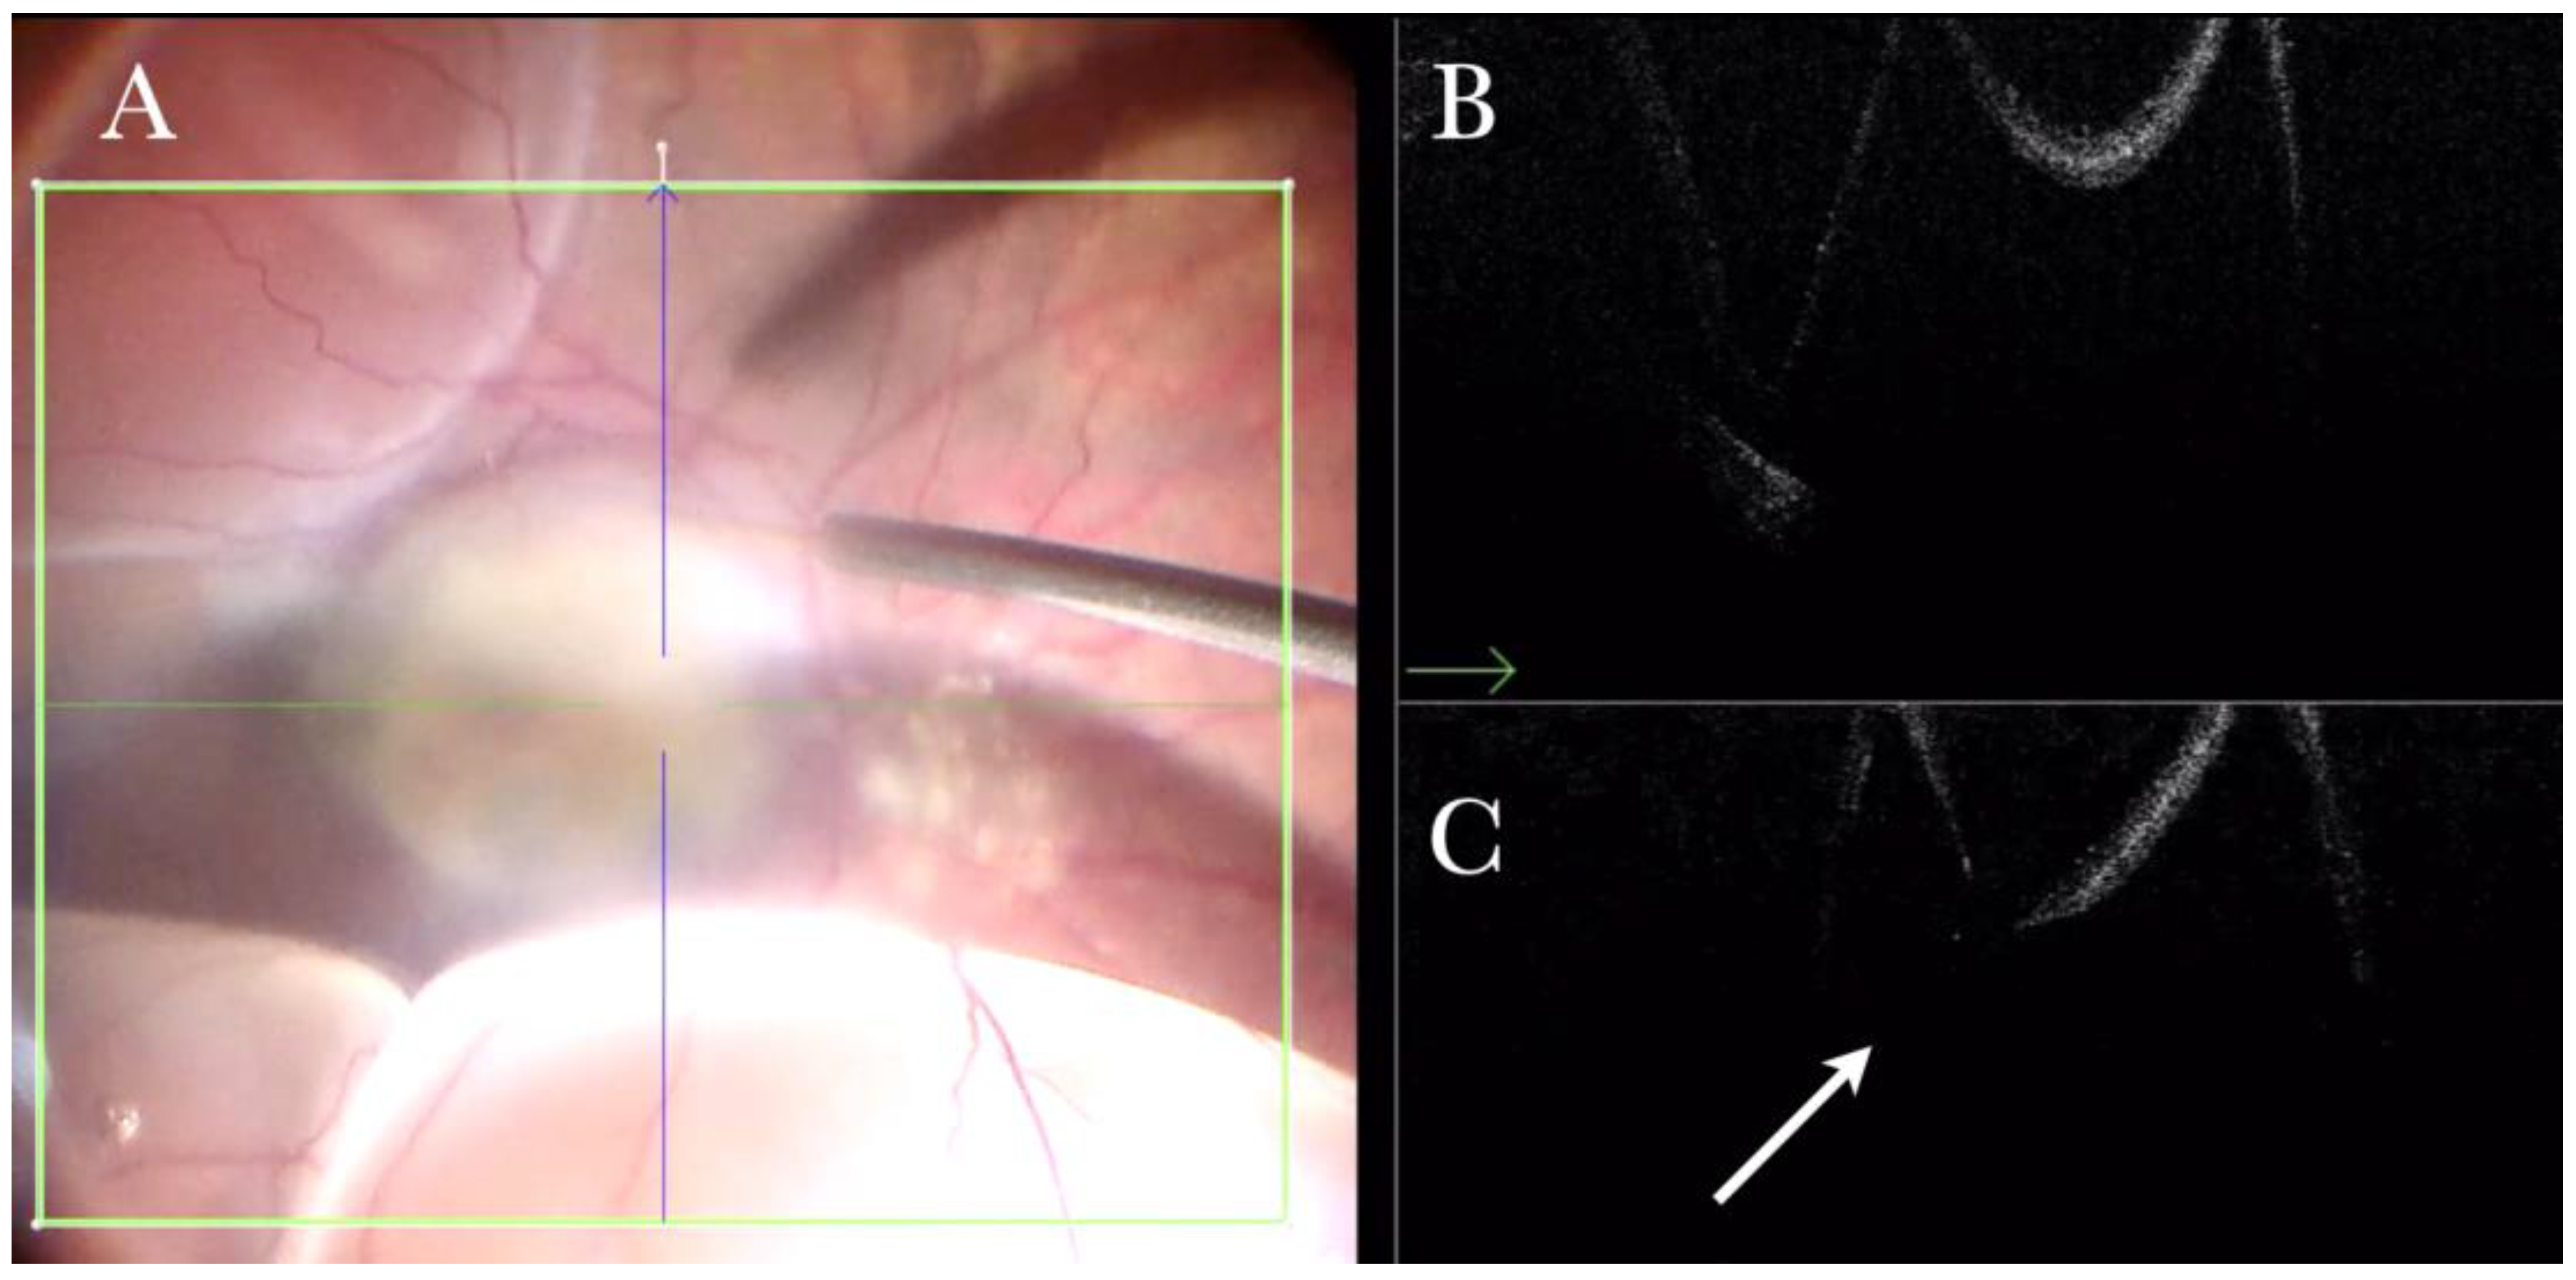

3.6. Submacular Surgery and Autologous Transplantation of Retinal Pigment Epithelium (RPE) and Choroid in Exudative Maculopathy

We performed 30 (11.32%) transplantations of the choroid and retinal pigment epithelium for exudative maculopathies. The i-OCT was useful in showing whether an FTMH was iatrogenically induced during the RD (Figure 22), and in displaying the correct position of the patch in the subfoveal area (Figure 23) by excluding the presence of subretinal PFCL (Figure 24).

Figure 22.

(A) Microscope view of the macular area in a case of autologous choroidal transplant. The surgeon is inducing a retinal detachment by injecting a balanced salt solution (BSS) through a 41-gauge needle into the macular area. (The green box indicates the field-of-view of the OCT scan, the green and blue lines within the green box show the vertical and horizontal scan planes). (B) The intraoperative optical coherence tomography (i-OCT) horizontal (green arrow) scan shows the detached macula. (C) The i-OCT vertical scan shows the detached macula with a full-thickness macular hole (FTMH) (white arrow) induced during the injection of BSS. The FTMH was not visible through the microscope and could be managed during surgery.

The i-OCT guided the surgeon in evaluating the macular status in real time, and in discriminating between iatrogenic and primary holes. Furthermore, at the end of the surgery, we could assess the presence of subretinal PFCL bubbles, the correct position of the patch, and the retinal status (flat vs. not flat).